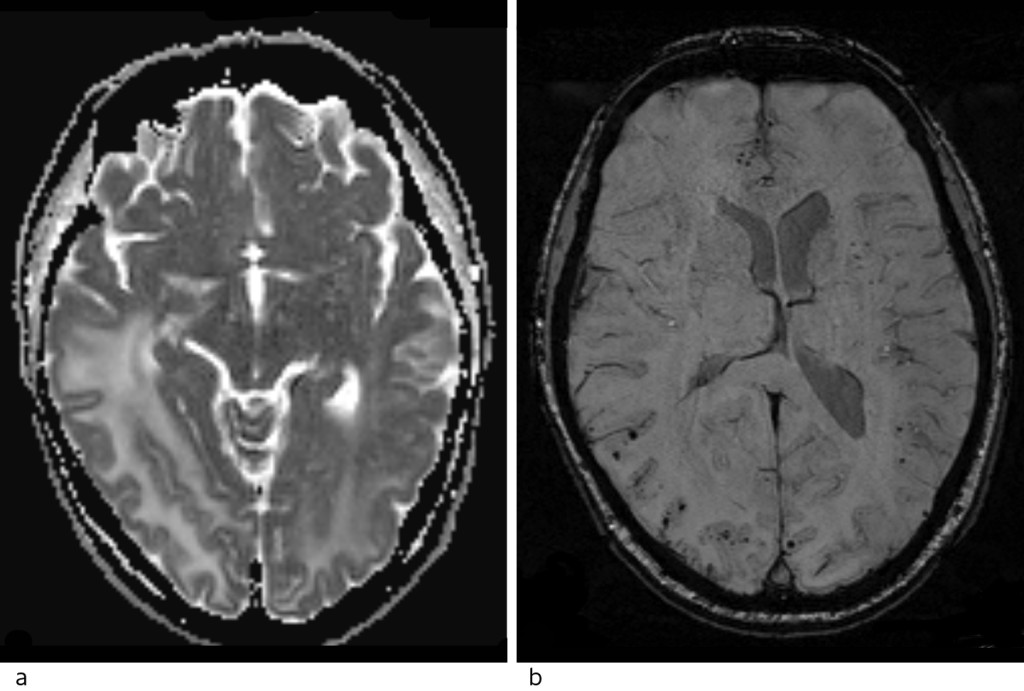

Head CT scans of the patient were taken with and without intravenous contrast. Low attenuation indicative of oedema in the white matter was seen in the occipitotemporal regions, being more pronounced on the right side with a mass effect and displacement of the midline towards the left (Fig. 1).

Figure 1 Head CT scan axial section (a) and coronal section (b) show extensive low-density changes that may be consistent…

Figure 1 Head CT scan axial section (a) and coronal section (b) show extensive low-density changes that may be consistent with oedema occipitotemporally on the right side and occipitally on the left side. No haemorrhaging is seen.